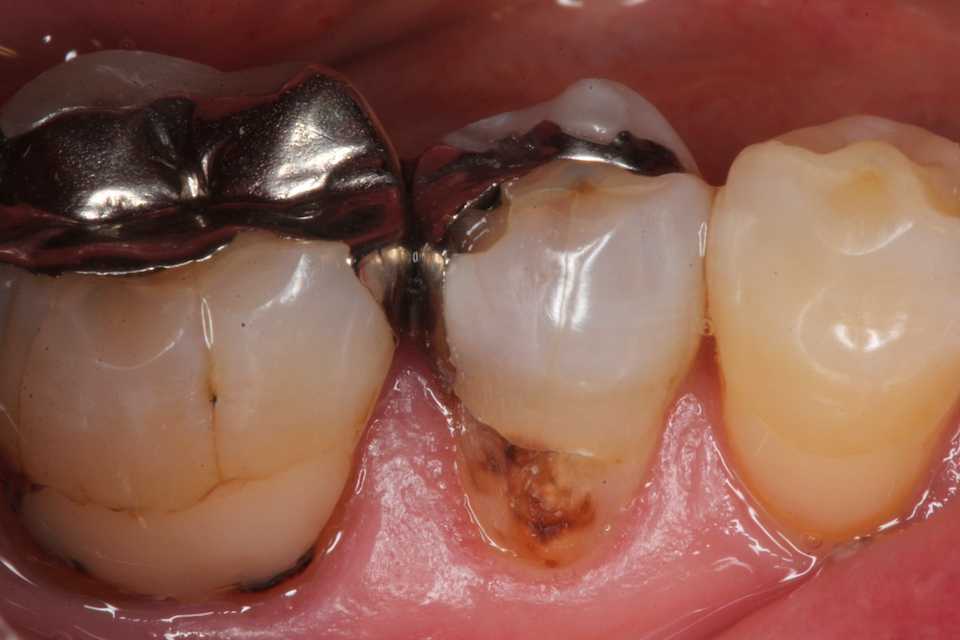

50代女性、右下5、インレー2次カリエス

では時系列でどうぞ